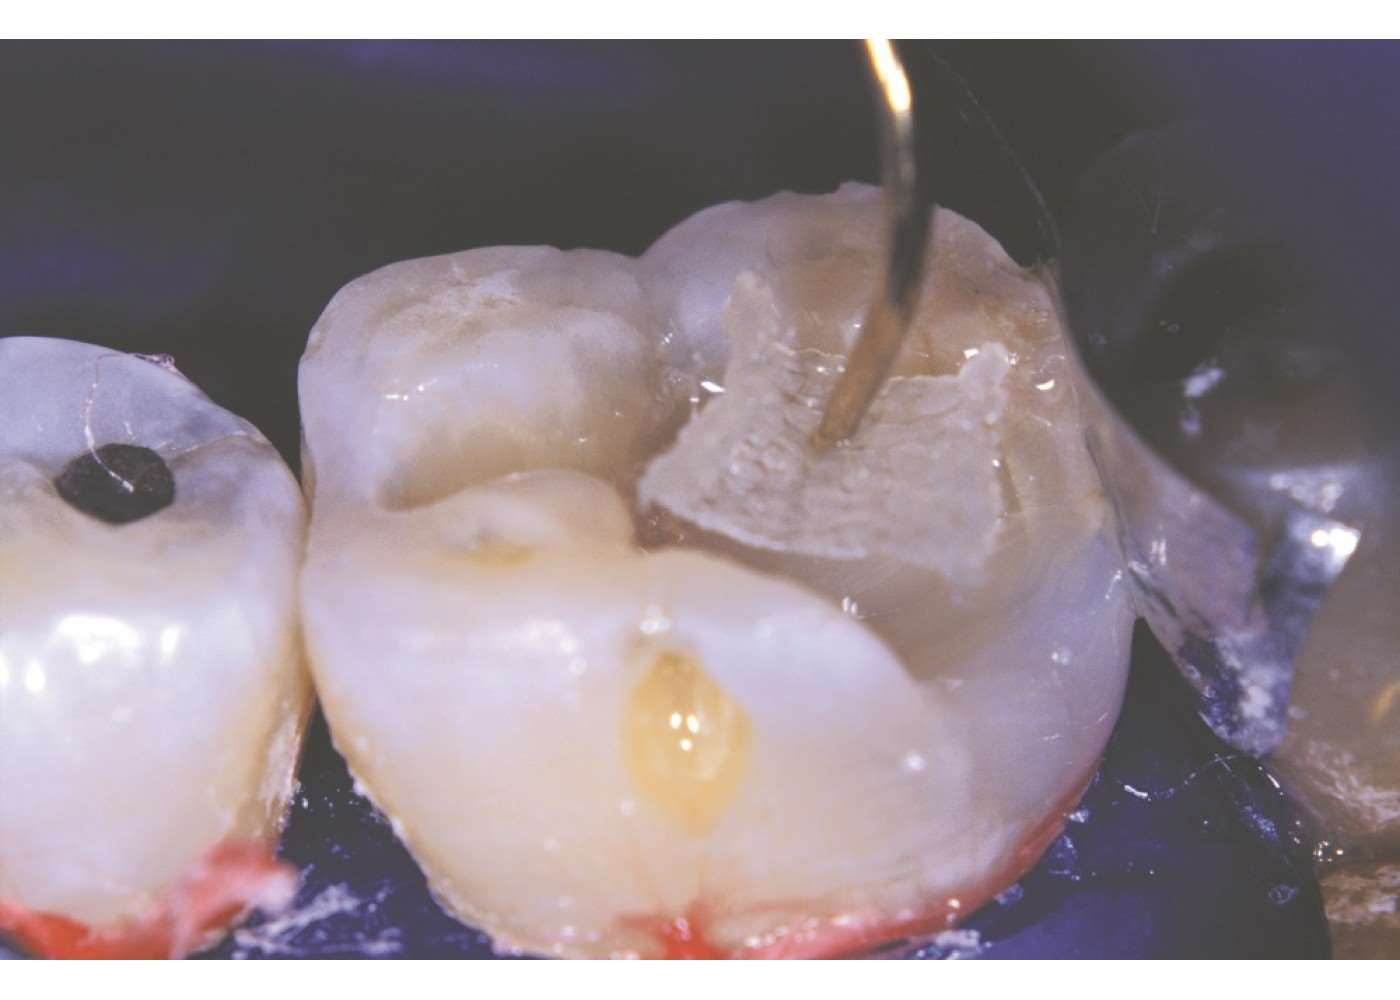

Η ειδική πλέξη σε συνδυασμό με το υλικό κατασκευής – ίνες που χρησιμοποιούνται για την κατασκευή αλεξίσφαιρων γιλέκων και προστατευτικής πανοπλίας για το στρατό – κάνει το Ribbond εξαιρετικά ανθεκτικό στη θραύση και είναι κατάλληλο για πολλές οδοντιατρικές εργασίες όπως: ναρθηκοποίηση, ενδορριζικούς άξονες, γέφυρες σε μία επίσκεψη, προσωρινές γέφυρες, αποκαταστάσεις ρητίνης σε μεγάλες κοιλότητες, διατήρηση κλείσιμου διαστήματος και σταθεροποίηση σε περίπτωση τραύματος.